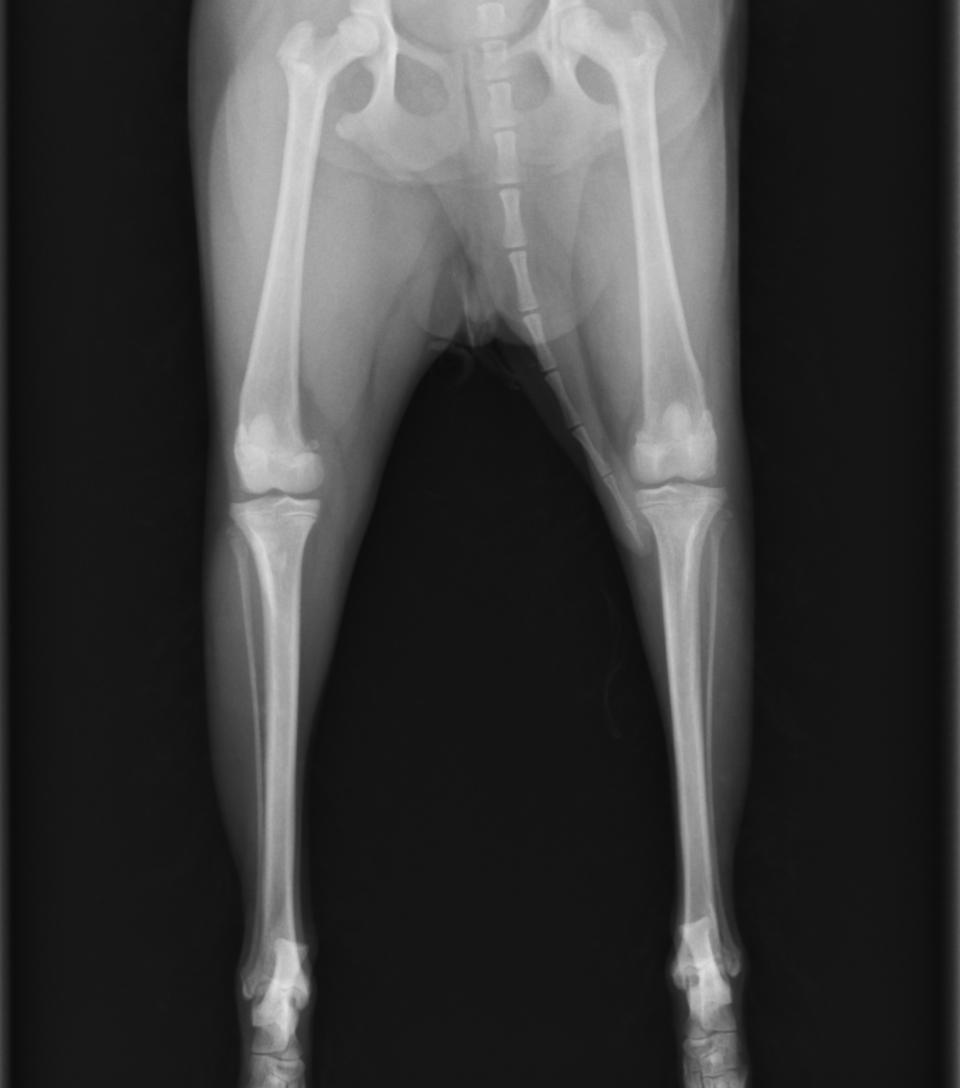

膝蓋骨内方脱臼(MPLといいます)は小型犬の後肢に影響を与える最も一般的な整形学的疾患の一つです。MPLの多くが小型犬であり、外傷なしで生まれつきもしくは生後早い段階で発生するため、遺伝的要因も関与している可能性が示唆されています。 MPLの要因は一つではなく、さまざまなことが複合的に合わさることで起きています。 1. コクサ・ヴァラ 大腿骨近位の内旋。 2. 大腿骨の遠位3分の1が内側に反っている。 3. 滑車溝の内側壁が浅いか欠損している。 4. 内側顆が低形成で、関節が傾いている。 5. 脛骨遠位端は外旋しているにも関わらず、脛骨粗面は内側への捻れている。 6. 脛骨近位部の内側への湾曲。 7.脛骨遠位端は外旋しているにもかかわらず、結果的に足先が内旋している。 このように骨の形態学的な異常から脱臼することがわかってきていますが、まだはっきりとしたことはわかっていません。

MPLではシングルトン分類というグレーディングシステムが一般的に利用されます。 Grade1:通常時には脱臼しないが、徒手によって脱臼がおきる。手を外すと正常位置に戻る。 Grade2:基本時にははまっているが、膝の屈伸や徒手により外れる。膝の屈伸や徒手で元に戻る。 Grade3:基本的に脱臼してしまっているが、徒手によって戻すことができる。手を離すと脱臼する。 Grade4:常に脱臼していて、徒手によっても戻すことができない 一般的にグレードが高いほど重症度が高いですが、必ずしも症状と一致しないのが難しいところです。 症状には時々跛行(ケンケンすること)する間欠的跛行と呼ばれるものから、完全に上げてしまって足をつくことができない(挙上といいます)状態などが挙げられます。お姉さん座りのように足を投げ出す、足を後ろに伸ばす仕草などが見られることもあります。 しかし、多くのMPL患者では症状がなく経過していきます。 膝蓋骨が脱臼することで膝の硝子軟骨というツルツルの軟骨が削れてしまい、その下の軟骨下骨が露出し、痛みになります。その後、その部分を自ら修復しようと繊維軟骨が覆っていきますが、その後関節炎が進行していきます。 そのような患者の中には中高齢になった段階で関節炎が起きて痛みが出るケースも見られます。また、そのほかにも膝の中の前十字靭帯が断裂して痛みが出て足をつくことができなくなったり、腰を痛めてしまったり、前肢を痛めてしまったりという患者が一定数います。

そのため、理想的には関節炎がなるべく少ない時期、つまり脱臼回数が少ないタイミングで外れないようにしてあげることが、関節炎を予防するために最も良い方法となります。 治療法には大きく分けて、内科療法と外科療法の二つに分かれますが、根本的な治療は外科療法となります。 外科には ①滑車溝形成術(溝を深くする) ②内側支帯リリース術(内側の筋肉や靭帯を緩める) ③外側支帯縫縮術(外側の筋肉や靭帯を縫い縮める) ④脛骨粗面転移術(パテラがくっついてい脛骨粗面というところを外側にずらす) ⑤内旋制動術(脛骨が内側に捻じれないように外に引っ張る) などを組み合わせて行われます。Grade4などの重症例に関しては矯正骨きり術と呼ばれる術式が適応となることもあります。

術後は2週間後に抜糸+レントゲン、その後2週間後にレントゲン、1ヶ月後にレントゲン撮影で一旦終了となります。2ヶ月を目処に通常の運動量に戻していきます。両側脱臼の際には両側同時に実施することを推奨しています。